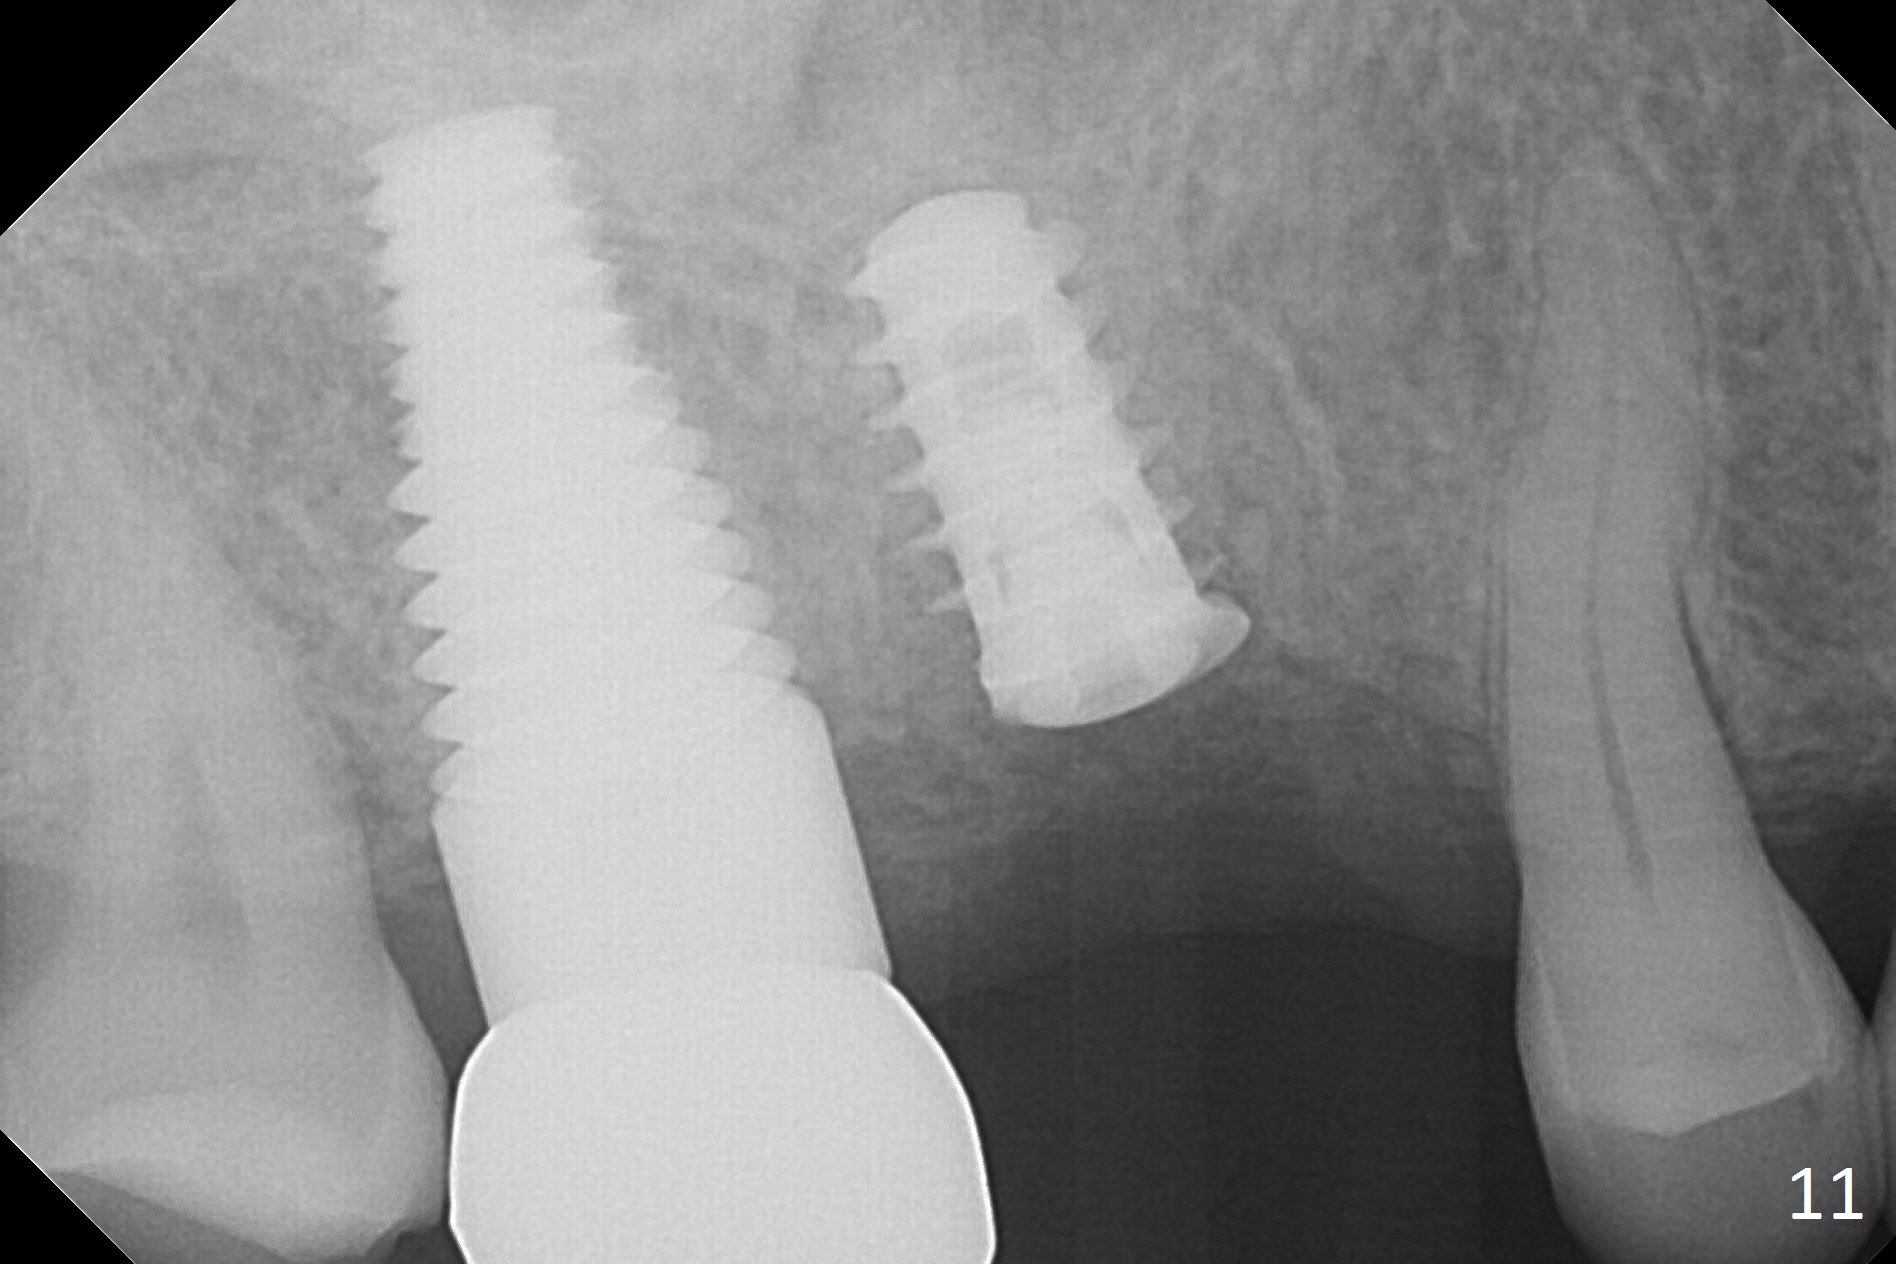

In fact, local anesthesia is required to remove the healing abutment. The gingival cuff is apparently healthy. The implant does not turn when torque reaches 45 Ncm. After placing a healing screw, PAs seem to show that the implant is osteointegrating (Fig.10,11).